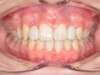

Cas 4 : Description

Chevauchement sévère. Traitement multibague sans extraction.

Avant

Après